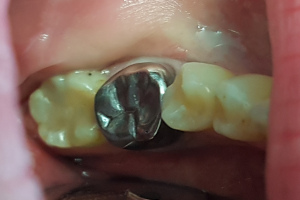

Die Metalle/Schwermetalle vor allem das Amalgam binden über eine kovalente Bindung an schwefelhaltige Proteine/Enzyme und blockieren damit vollständig deren Funktion. Der mineralhaltige Speichel ist außerdem eine hervorragende elektrolytische Lösung. In dieser fließen die Elektroden unterschiedlicher Metalle und verursachen einen Stromfluß, wodurch die Metalle korrodieren.

Im heutigen Zeitalter sind wir durch, zum Beispiel Ausbreitung des WLAN, unweigerlich unterschiedlichen Frequenzen sowie elektromagnetischer Strahlung ausgesetzt. Metallversorgungen und auch Titanimplantate wirken unter diesen Bedingungen wie kleine Antennen mit Sender- und Empfängerwirkung. Dies stört die Nervenzellfunktion erheblich. Durch die dadurch bedingte Temperaturerhöhung des umliegenden Gewebes wird die Strahlung weiter verstärkt. Gesundheitliche Beeinträchtigungen wie zum Beispiel Schlaflosigkeit, Kopfschmerzen oder Tinnitus sind die Folge. Um dem entgegenzuwirken sollte auf Metalle im Mund verzichtet werden bzw. bestehende Metallversorgungen entfernt und durch keramische Versorgungen ersetzt werden.